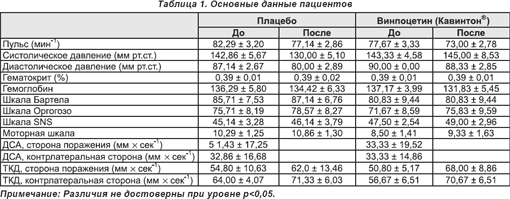

При подготовке данных к завершающему анализу двое пациентов были исключены (по одному из групп плацебо и активной терапии) на основании (а) технических проблем (при проведении ПЭТ в поле зрения был захвачен недостаточный объем ткани головного мозга) и (б) подозрения в отношении развития острого цереброваскулярного явления в период между двумя сессиями сканирования. Таким образом, заключительные группы пациентов в ходе анализа изображений состояли из 7 (группа плацебо) и 6 субъектов (групп активной терапии). Подробные индивидуальные данные пациентов представлены в таблице 1.